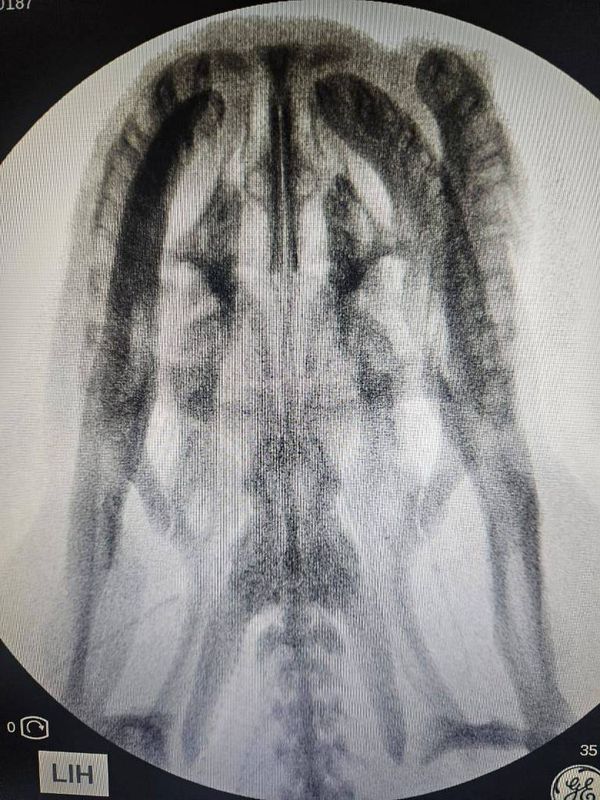

Raio-X da sucuri feito pela Polícia Científica de Mato Grosso do Sul mostra a integridade da cabeça da cobra

Raio-X da sucuri feito pela Polícia Científica de Mato Grosso do Sul mostra a integridade da cabeça da cobra Crédito: Divulgação/Polícia Cientifica MS

"Nós realizamos exames por raio-x na cobra, que poderiam indicar projéteis alojados ou quebramento de ossos, mas nada foi encontrado e descartamos efetivamente morte violenta ou por causas externas", disse o diretor do Instituto de Criminalística, Emerson Lopes dos Reis.